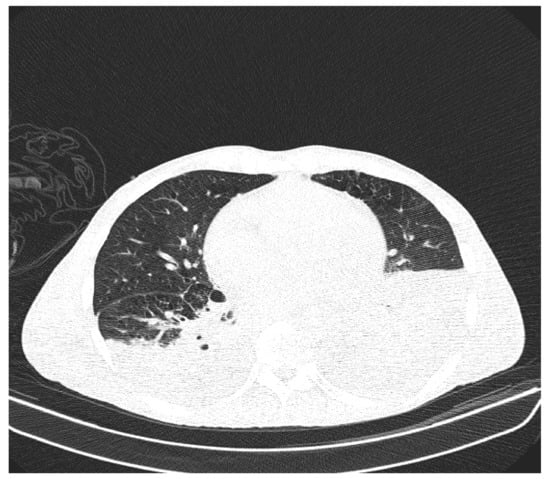

Due to the worsening general conditions, the patient was submitted to thoracic, abdominal, and pelvic computer tomography scans, which revealed:

• Numerous central and peripheral emphysema bubbles, with regular thin walls, located at the level of both lung fields, the largest located apically superior bilaterally;

• Numerous bronchiectasis with variable dimensions, some with free lumen, located in both upper lobes, in the right middle lobe and lingular segments;

• Pulmonary condensation areas in the middle and posterobasal segments of both lower lobes, especially on the left side (Figure 4).

Figure 4. Patient’s computer tomography: pulmonary condensation areas in the middle and posterior-basal segments of both lower lobes, especially on the left side.

• Bilateral mediastinal, laterotracheal lymphadenopathy (maximum axial diameter: 13 mm on the right side and 11 mm on the left side), right hilar (maximum 13 mm), and infrared (maximum 18 mm);

• Bilateral posterobasal pleurisy (liquid blade with a thickness of 40 mm on the right side and 41 mm on the left side) (Figure 5).

Figure 5. Patient’s computer tomography: bilateral posterior-basal pleurisy.